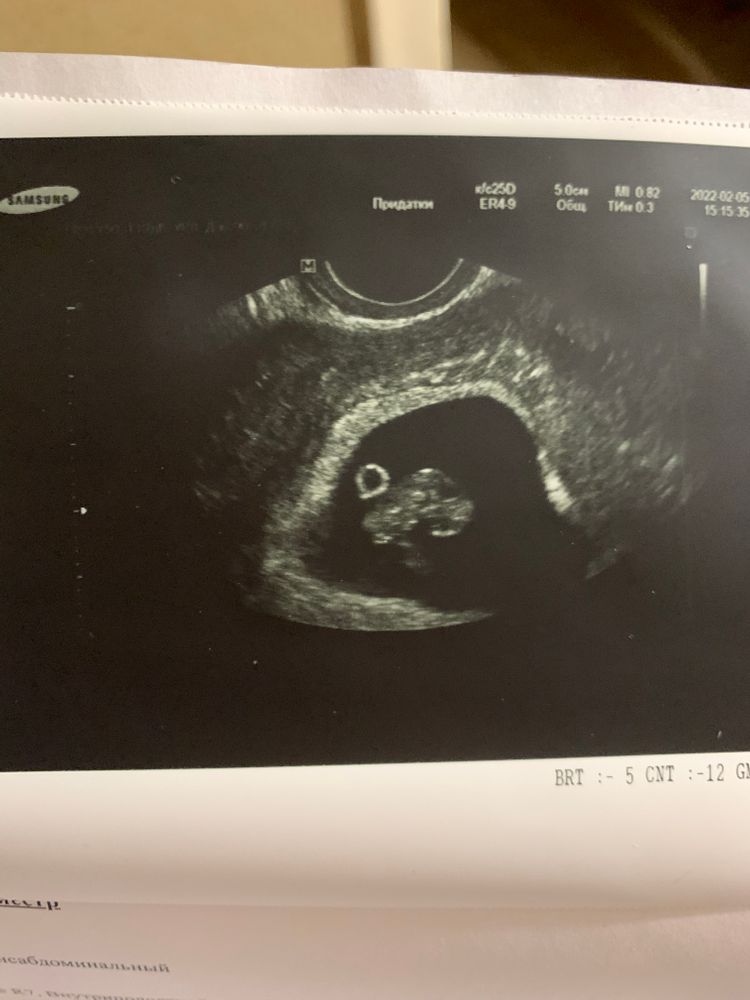

Были на узи, по месячным срок 7 недель, 5 дней, ктр 17мм. Сб 142уд/мин. Такой вопрос, нормально ли, что эмбриончик «плавает» где-то в середине? У кого ни посмотрю, «прикреплён» к краю

В любом случае он где-то прикреплён, к передней или задней стенке, просто так они не плавают😂 а эмбриончик красивенький у вас😍 у меня тоже 8 недель ☺️

Мороз, пишут, что к передней стенке, на 7 неделе было к задней стенке) непонятно) да просто смотрю у кого-то, у всех будто «прилеплен») вот и задаюсь вопросом)